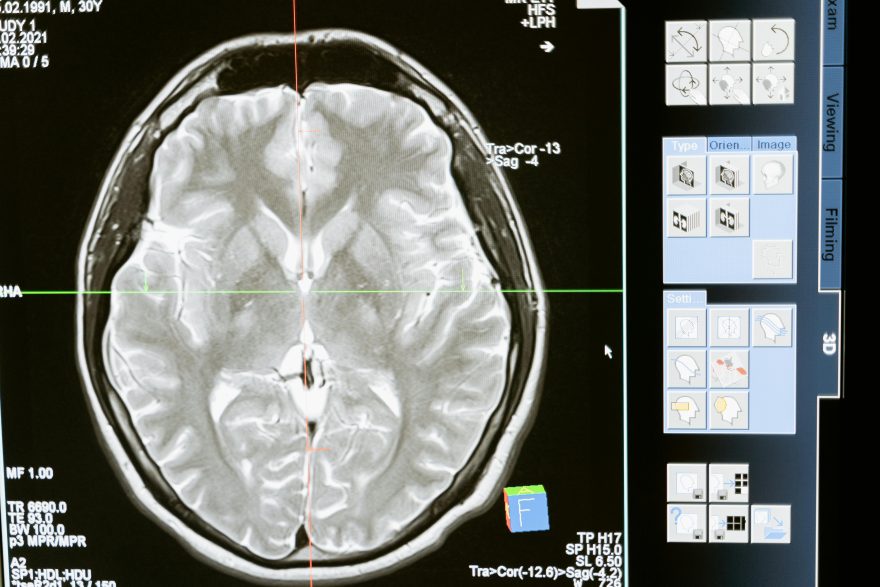

La autorización de la FDA bajo el esquema de investigational device exemption (IDE) legitima el paso de la teoría a la práctica clínica. Neuralink ya había probado sus implantes en contextos de movilidad —permitiendo controlar ordenadores o brazos robóticos—, pero el salto hacia la traducción de pensamientos en lenguaje escrito abre una dimensión radicalmente distinta.

El ensayo de octubre representa uno de los usos médicos más ambiciosos de las interfaces neuronales hasta la fecha, y busca comprobar no solo la precisión en la decodificación de señales, sino también la seguridad a largo plazo de los implantes en regiones cerebrales asociadas al habla.